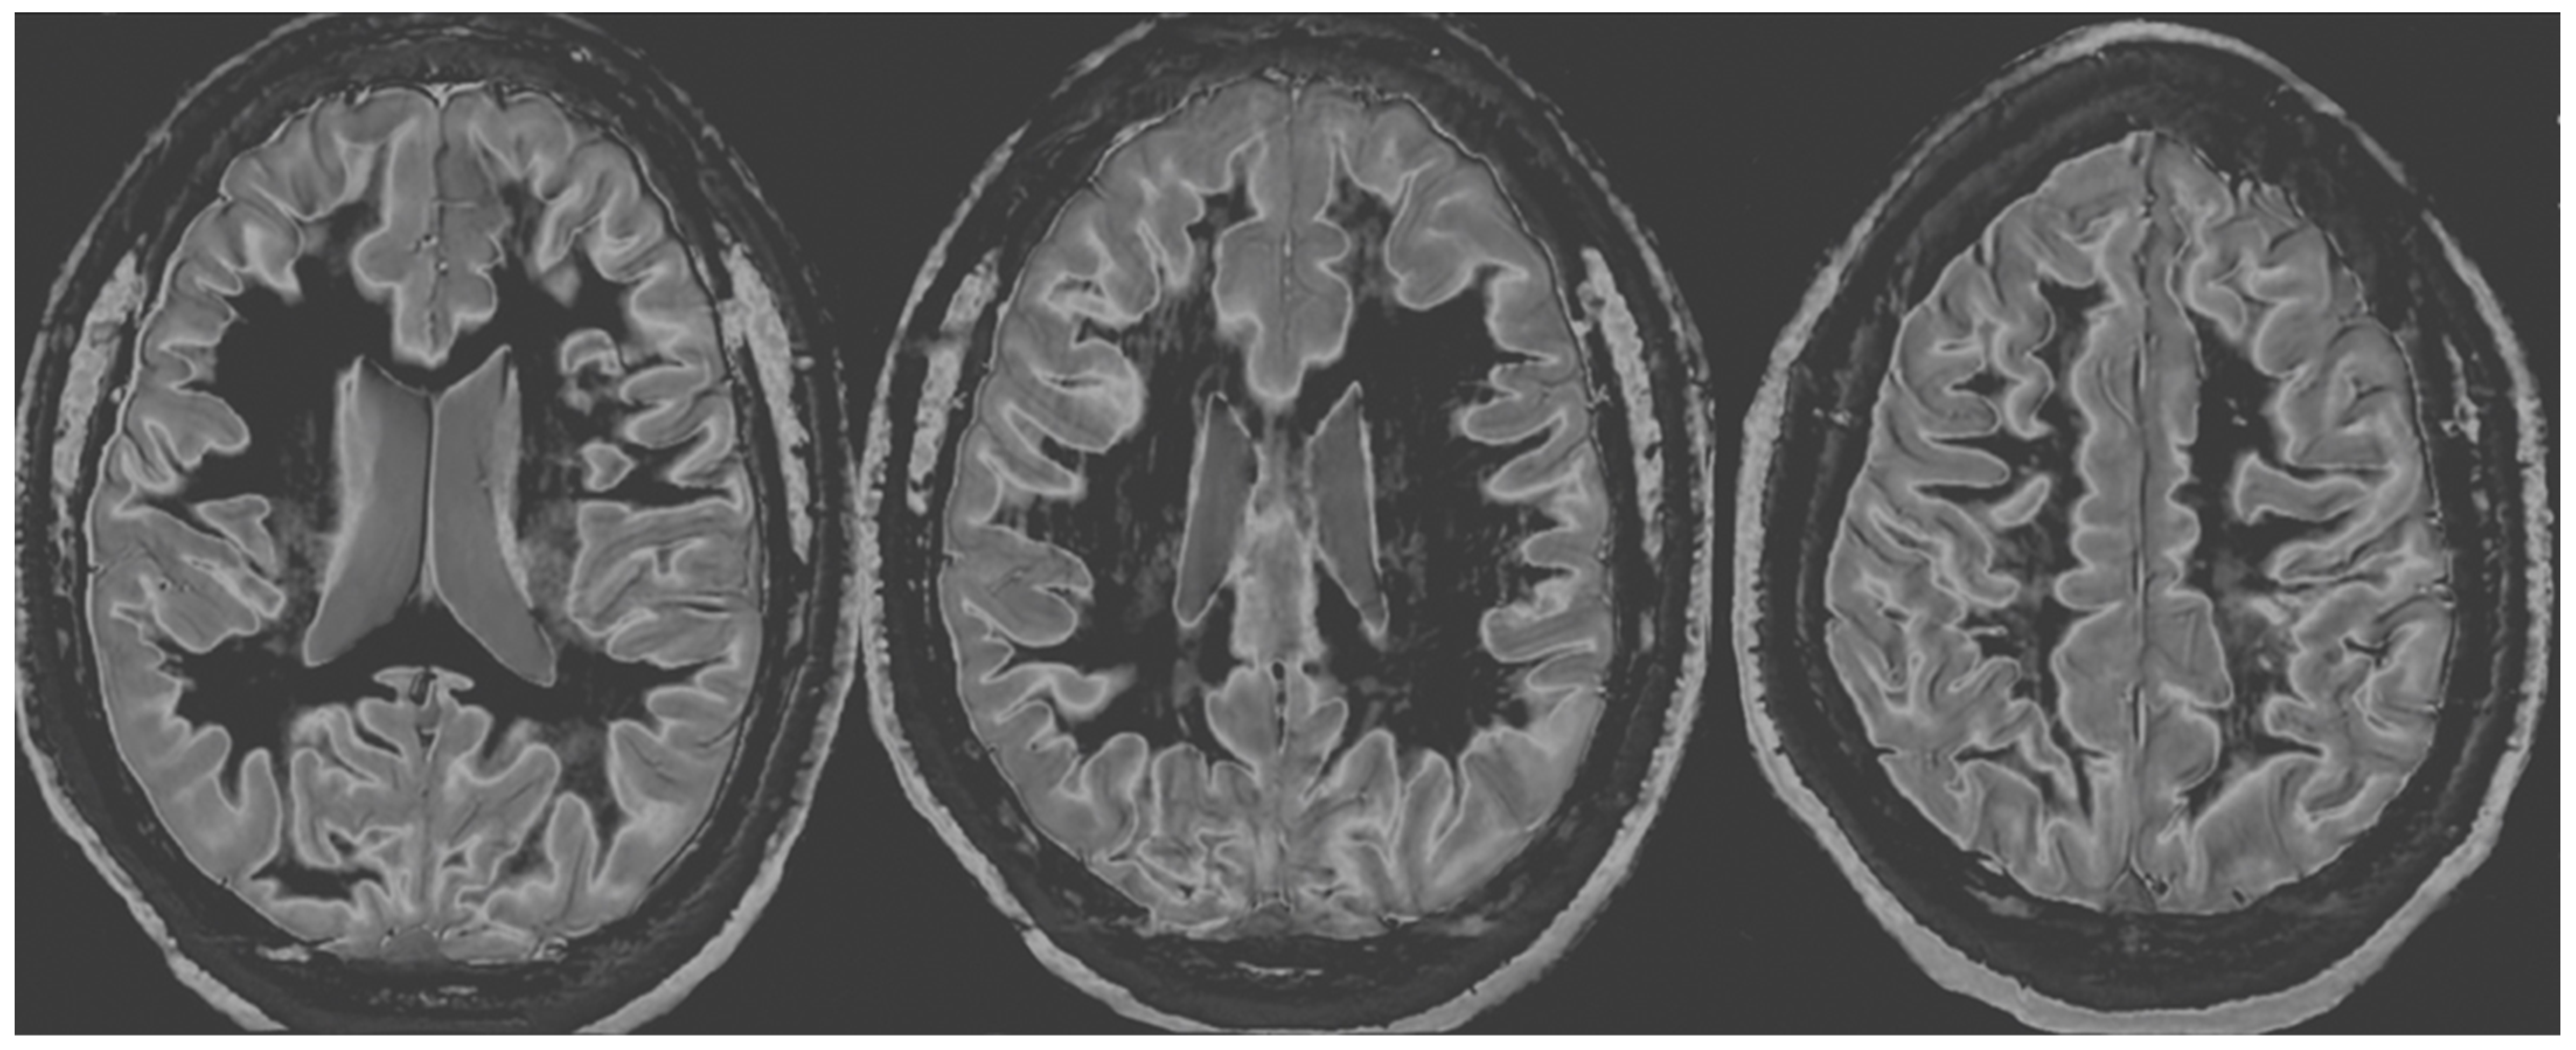

Figure 6 and Figure 7 show T2-FLAIR images (upper rows) with positionally matched dSIR images (lower rows). No abnormalities are seen in the white matter on the T2-FLAIR images, but very extensive high signal abnormalities are seen in the white matter of the corresponding dSIR images. There is relative sparing of the anterior central corpus callosum and, to a lesser extent, the posterior central corpus callosum. There is also some sparing of the peripheral white matter in the cerebral hemispheres.

Overall, the MRI findings in Case 2 are very similar to those in Case 1, as shown in Figure 4 and Figure 5. They have been described as a whiteout sign. This often involves 80% or more of the white matter in the cerebral and cerebellar hemispheres having an abnormal high signal appearance.

One patient with a history of a severe drug overdose and another with a history of attempted suicide by asphyxia were examined with MRI nine months and two years afterwards using T2-FLAIR and dSIR sequences. In both cases, no abnormalities were seen in their white matter with T2-FLAIR sequences, but very extensive changes were seen in their white matter using dSIR sequences. In both cases, the changes were bilateral and symmetrical and involved the cerebral and cerebellar hemispheres. There was sparing or relative sparing of the anterior central corpus callosum and adjacent white matter and, to a lesser extent, the posterior central corpus callosum. There was also sparing of the white matter in the periphery of the cerebral hemispheres.

Figure 7. Case 2 was examined two years after his asphyxial episode. Comparison of positionally matched T2-FLAIR images (upper row) and narrow mD dSIR images (lower row). No abnormality is seen on the T2-FLAIR images, but there are extensive areas of high signals in the central white matter of the brain (lower row). Only some of the peripheral white matter on the lower images appears darker and looks more normal on the dSIR images.